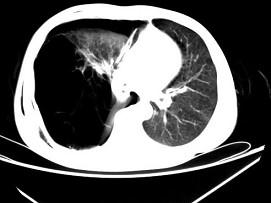

问题 男,32岁,被车撞伤后1小时,请结合影像图像选择其最可能的诊断为 ( )

选项 A、右侧肺大疱并皮下纵隔气肿 B、支气管断裂 C、右肺不张 D、右侧气胸并皮下纵隔气肿 E、右侧气胸

答案 D